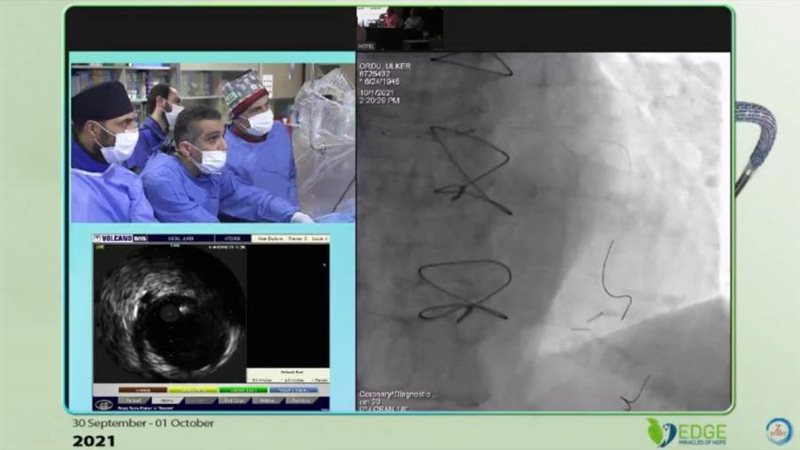

أعلنت الهيئة العامة للرعاية الصحية، عن نجاح رئيس قسم القلب بمستشفى النصر التخصصي للأطفال التابعة للهيئة بمحافظة بورسعيد الدكتور طارق رشيد، في إجراء قسطرة قلبية معقدة لعلاج إحدى الحالات المرضية بمستشفى ميموريال Memorial Hospital في مدينة إسطنبول بدولة تركيا.

وأضافت الهيئة، أنه جاء ذلك خلال مشاركة استشاري القلب الدكتور طارق رشيد في مؤتمر للقسطرة التداخلية المعقدة بمدينة إسطنبول في تركيا، لافتة إلى أن الهدف الرئيسي من إجراء هذه العملية هو تبادل الخبرات بين مصر وتركيا في مجال معالجة أمراض القلب باستخدام القساطر التشخيصية أو العلاجية كأحدث التقنيات العلاجية وفق ممارسات الصحة العالمية.

وقال الدكتور طارق رشيد، استشاري القلب والقسطرة وعضو هيئة التدريس بكلية الطب جامعة عين شمس ورئيس قسم القلب بمستشفى النصر التخصصي للأطفال ببورسعيد، أن الهدف الرئيسي من إجراء هذه العملية في مستشفى ميموريال بإسطنبول تركيا هو نقل المعرفة والعلم والخبرات التي اكتسبها على مدار سنوات عمله الممتدة لعلاج أمراض القلب وفق أحدث الإرشادات والبروتوكولات العلاجية المعتمدة دوليًا إلى الكوادر الطبية التركية وتدريبهم على إجراء مثل تلك العمليات النادرة، مؤكدًا أن الأطباء المصريين لا يقلون كفاءة عن نظرائهم في دول العالم المتقدمة طبيًا.